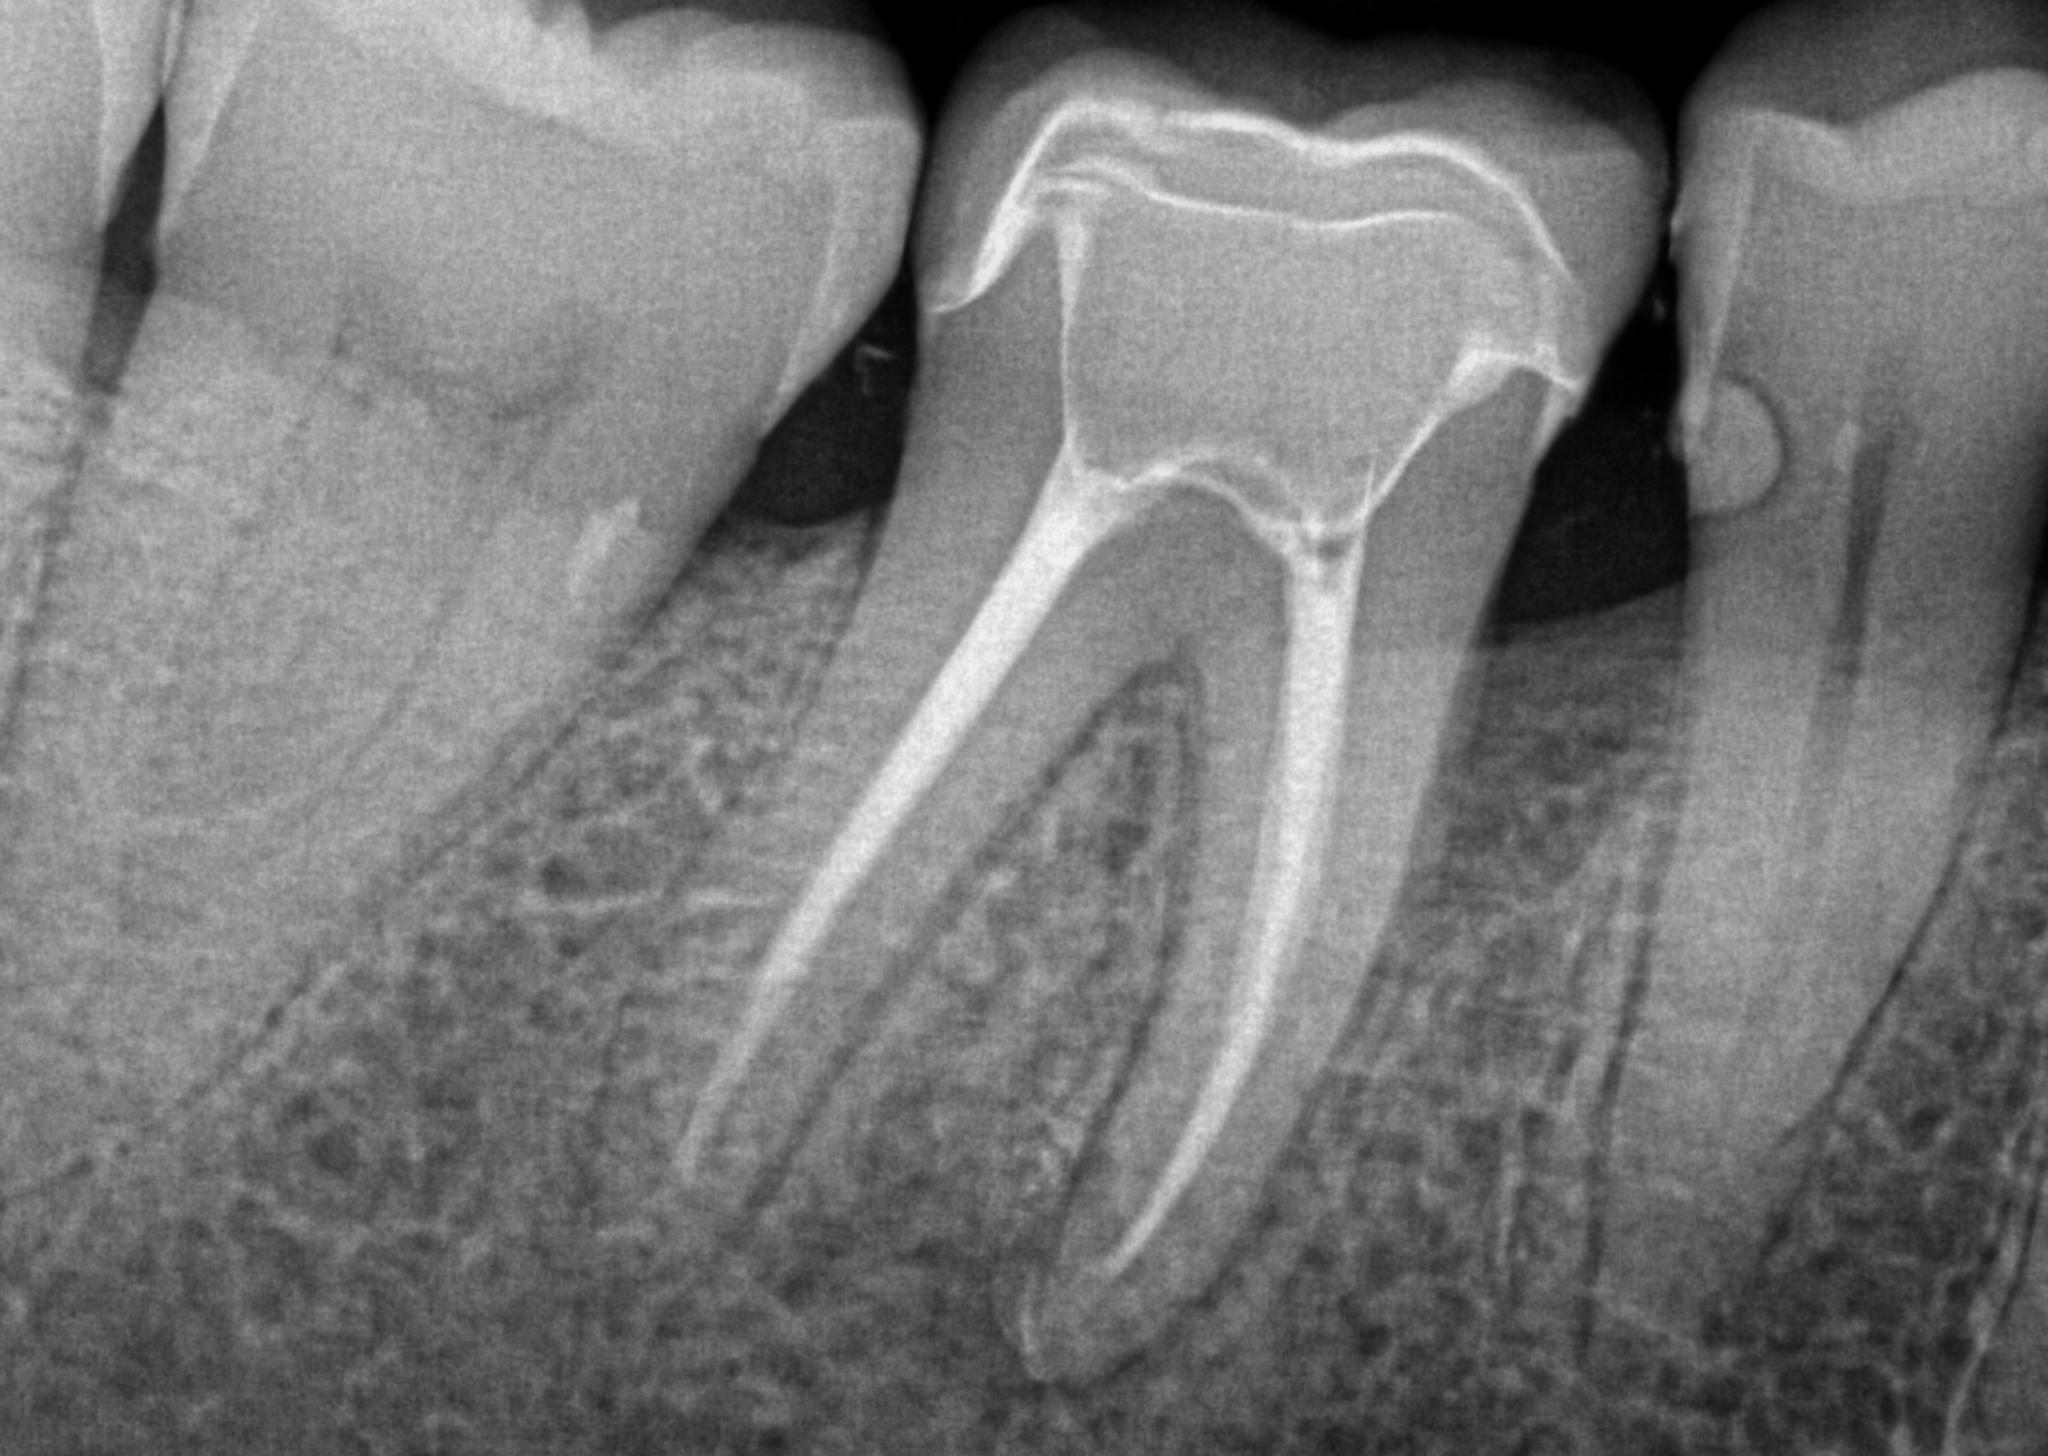

Root Canal

Alleviate tooth pain and save your natural teeth with our expert Root Canal Treatment. This procedure involves removing infected or damaged pulp from inside the tooth, then cleaning and sealing it to prevent further infection. Our advanced techniques and modern equipment ensure the process is as comfortable and efficient as possible. Trust the skilled team at Hamilton Care Dental Centre to provide effective root canal therapy, restoring your oral health and maintaining your beautiful smile. With our gentle approach, we aim to make your experience stress-free and painless, allowing you to return to your daily activities quickly. Don't let tooth pain disrupt your life—schedule your root canal treatment with us today.